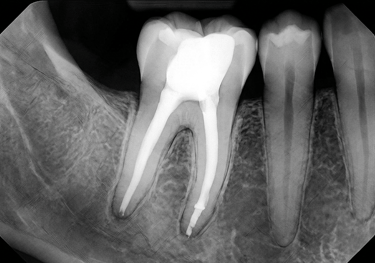

Gentle, precise treatment to relieve pain, treat infection, and preserve your natural tooth.

Root Canal Treatments